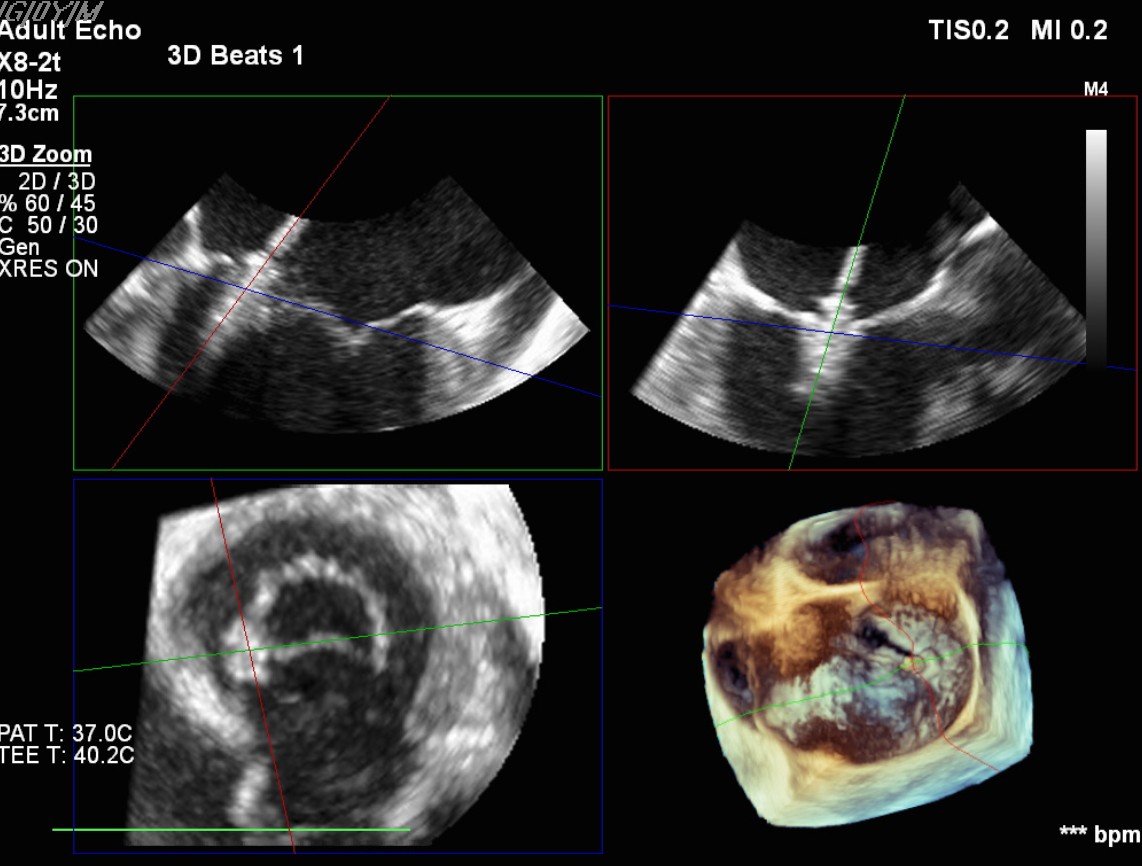

Transcatheter Edge-to-Edge Repair (Mar 27): TEE demonstrated severe mitral regurgitation with low cardiac output (~2 L/min). Two G4 XTW MitraClips were implanted successfully, improving hemodynamics.